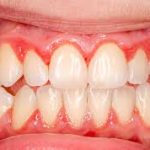

- Diş plakları ve tartar (diş taşı) birikimi, gingivitis ve periodontitise yol açar.

- Gingivitis: Sadece dişetinde inflamasyon vardır, başlangıç aşamasında genellikle çekilme görülmez.

- Periodontitis: Dişeti ve alveolar kemiğin kaybına yol açan ileri inflamasyon, diş eti çekilmesinin en yaygın biyolojik nedenidir.